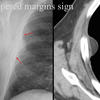

Tapered margins sign

Pleural or extrapleural origin

Tapererd margins sign

Pleural lipoma